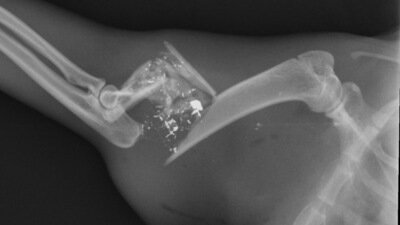

Régulièrement, des coups de feu sont tirés dans notre quartier à proximité de nos habitations. Plusieurs voisins ont été victimes de ses agissements en retrouvant des plombs dans leur piscine par exemple ou encore des coup de feu ayant été tirés sur des nids de frelons ou des oiseaux à proximité de leurs habitations. Dernièrement le chat d’un habitant du quartier a été la cible de coup de feu. Les blessures étaient si graves qu’il a fallu l’amputer de sa patte avant, entraînant un handicap conséquent et des frais vétérinaires très élevés.